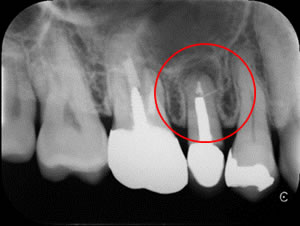

歯科用CT撮影による精密検査

歯科用CTは、X線での断層撮影を行い、コンピューターでのデータ処理・再構成によって、歯や顎骨の状態、神経の位置、血管の位置などを3次元画像で確認できます。

今まで見えなかった病巣や、解らなかった歯の形が鮮明に浮かび上がってきます。顕微鏡との併用により、根管治療の成功率アップに、特に再治療時の診断に大きな貢献をいたします。